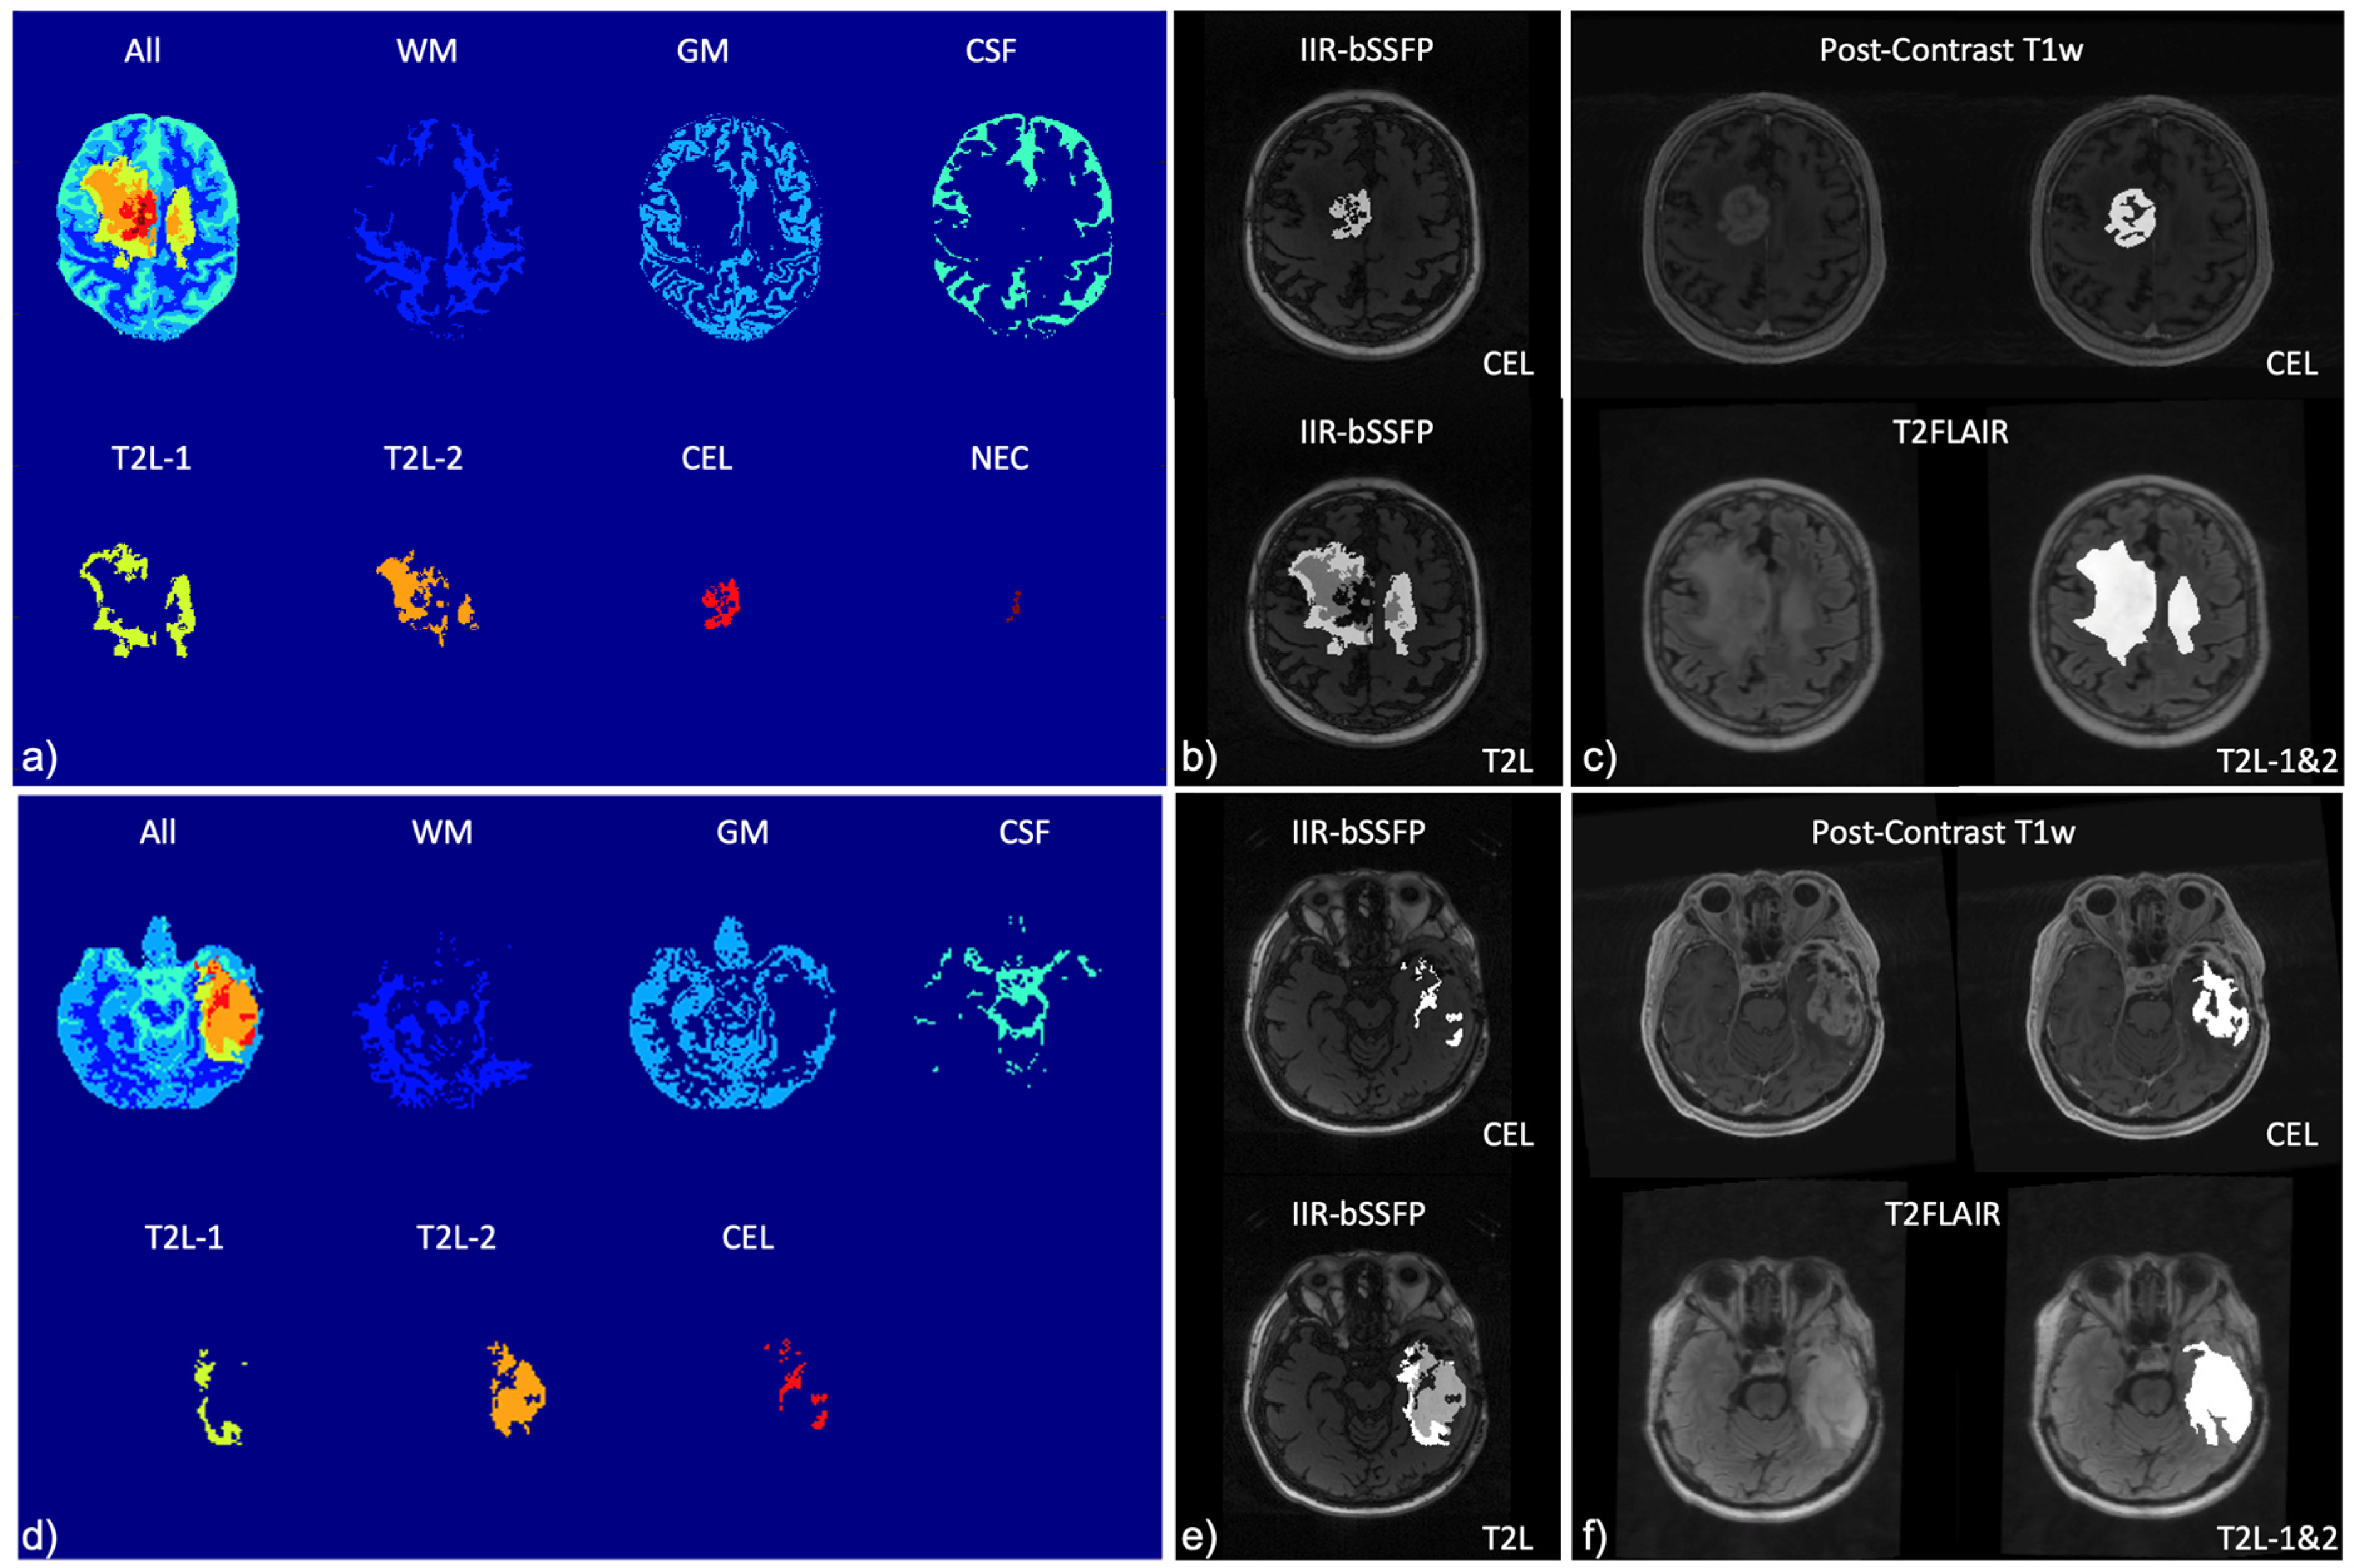

3. Results

| Mapping | WM | GM | T2L-1 | T2L-2 | CEL | NEC |

|---|---|---|---|---|---|---|

| 2D T1 (ms) | 1186.4 ± 110.5 | 1589.5 ± 331.7 | 1451.5 ± 317 | 1657.9 ± 409.3 | 1947.8 ± 465.6 | 2022.3 ± 459.3 |

| 2D T2 (ms) | 90.4 ± 2.7 | 117.5 ± 12.8 | 114.7 ± 14.2 | 138.2 ± 21.3 | 153.4 ± 47.6 | 152.0 ± 41.1 |

| 3D MWF (%) | 30.4 ± 3.4 | 9.5 ± 3.3 | 12.5 ± 9.3 | 2.3 ± 1.8 | 0.55 ± 0.4 | 0.15 ± 0.0 |

| IIR-bSSFP T1 (ms) | 797.5 ± 88.3 | 670.4 ± 60.2 | 610.9 ± 58.1 | 598.4 ± 77.8 | 958.8 ± 204.9 | 1876.7 ± 608.8 |

| IIR-bSSFP T2 (ms) | 22.0 ± 5.7 | 85.2 ± 8.8 | 62.9 ± 26.5 | 115.4 ± 11.2 | 121.5 ± 10.1 | 157.5 ± 42.0 |

| IIR-bSSFP MF (%) | 14.9 ± 2.5 | 8.7 ± 1.9 | 11.9 ± 3.8 | 5.5 ± 2.6 | 3.6 ± 2.0 | 1.6 ± 0.5 |

| Mapping | CSF | WM | GM | T2L-1 | T2L-2 | CEL | NEC |

|---|---|---|---|---|---|---|---|

| IIR-bSSFP T1 (ms) | 2990.4 ± 277.4 | 848.0 ± 135.5 | 912.4 ± 218.4 | 749.5 ± 217.2 | 883.8 ± 238.8 | 1300.7 ± 303.4 | 2696.6 ± 749.7 |

| IIR-bSSFP T2 (ms) | 218.1 ± 14.9 | 28.5 ± 5.3 | 83.1 ± 20.9 | 62.2 ± 22.4 | 94.1 ± 29.1 | 115.8 ± 19.1 | 190.7 ± 31.9 |

| IIR-bSSFP MF (%) | 1.0 ± 0.4 | 10.0 ± 2.8 | 5.3 ± 1.3 | 7.8 ± 3.4 | 3.4 ± 1.3 | 2.6 ± 1.0 | 2.2 ± 1.2 |